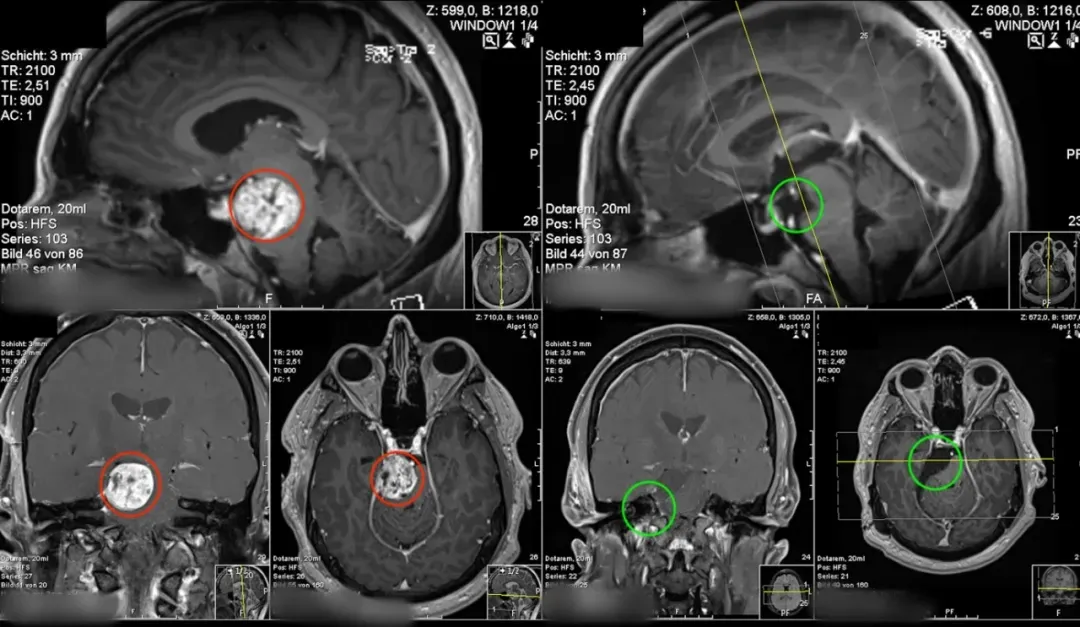

MRI图像呈现神经鞘瘤的典型结构,肿瘤直径约3 cm,与右腱膜及Meckel区关系广泛,并显著压迫和推移脑干,尤其影响上段脑桥及下段中脑。

肿瘤向背侧蝶鞍及右后斜突延伸,位于移位的动眼神经前方。脑后动脉与小脑上动脉也受肿瘤影响,正常位置发生改变。

(术前与术后MR对比)